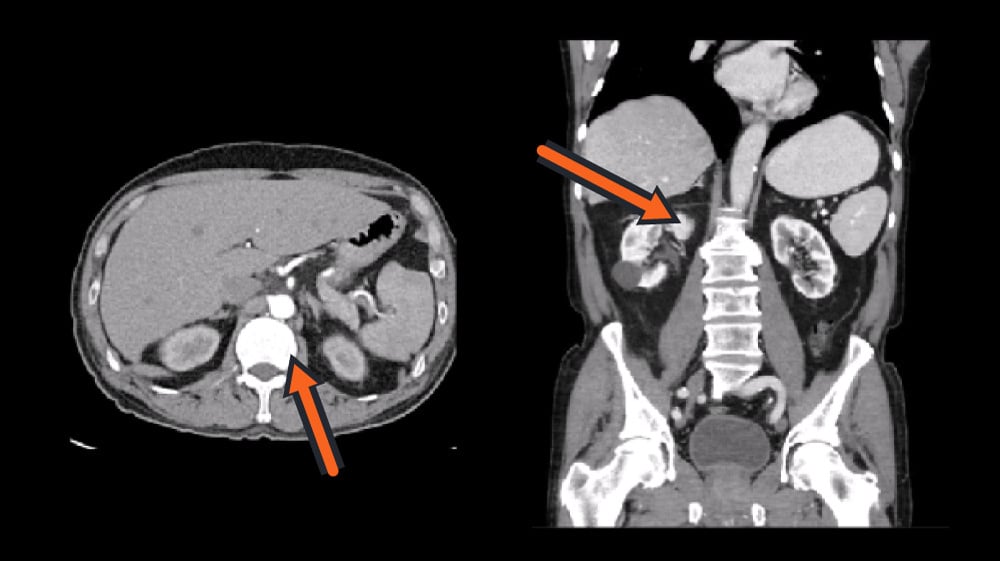

A still from the video lesson 'CT Pharynx, Larynx and Trachea' demonstrating the clear format used to help students orient themselves and identify key anatomic structures when reviewing CT scans.